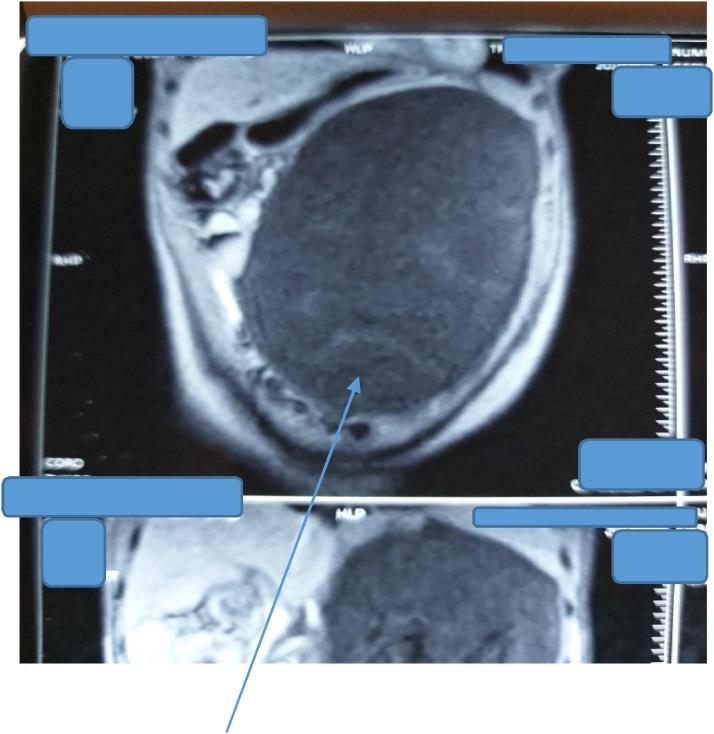

Two female patients aged 22 years and 65 years respectively, and an 11-year-old boy presented with giant pancreatic pseudocysts (>10 cm in diameter each) to our unit and were successfully managed. They all underwent exploratory laparotomy and cysto-gastrostomy with good outcome.

两名分别为22岁和65岁的女性患者以及一名11岁男孩因胰腺巨大假性囊肿(直径均>10 cm)前来我院就诊,并成功接受治疗。他们均接受了剖腹探查术和囊肿胃吻合术,效果良好。